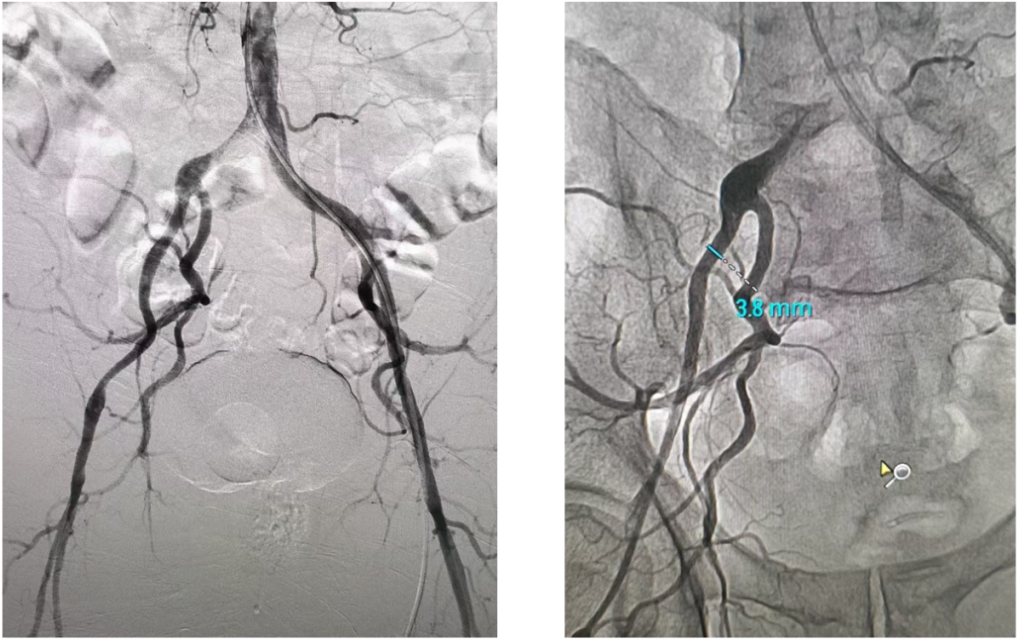

患者病史 术前超声提示:主动脉瓣退行性病变;中-重度狭窄并轻度返流;中-重度三尖瓣返流;中度肺高压 术前CT 三叶瓣,瓣叶增厚轻度钙化,右无交界有粘连,预计可以扩开,主动脉根部直径23.7mm,LVOT直径24.3mm,呈直筒型;双侧冠脉开口高度可,瓣叶长度小于冠脉开口上缘到主动脉根部的距离;窦部空间可,STJ、升主动脉内径可;主动脉水平夹角43.6°,非横位心;主动脉弓角、弓距可,左室内径可;外周入路无明显迂曲,有零星散状钙化,双侧股动脉内径可,均能通过20F大鞘,右股低分叉。 手术策略 推荐右侧股动脉为主入路使用20F大鞘,左侧股动脉为辅入路,右股分叉上方1cm穿刺;推荐使用22mm球囊预扩,预装AV26瓣膜,备AV29瓣膜,初始定位为真实瓣环上方3mm,瓣膜释放过程中释放张力使其自然下滑,工作位观察瓣膜稳定性,最终理想位置为零位;左右重合位:RAO23°CAU32°;右窦居中位:LAO5°CAU12°;左冠切线位:LAO34°CRA14°。 手术过程 术中右股动脉痉挛,内径变为3.8mm,遂更换左腋动脉入路;18球囊预扩,后植入AV26 ProStyle A®瓣膜;瓣膜精准释放于目标位置,超声显示无明显瓣周漏,血流动力学即刻改善。 术中右股动脉痉挛,内径变为3.8mm,更换左腋动脉 主动脉根部造影 18球囊预扩 初始定位 工作位观察 术后即刻表现:无瓣周漏,术后峰值压差10mmHg 术后3天复查超声峰值压差14mmHg Prostyle A®预装干瓣——助力临床最优化解决方案: 轻松过弓,精准可控:该病例经左腋动脉入路,输送系统较细的尺寸+柔顺的输送系统通过性能得到了很好的验证; 释放稳定:平衡的径向支撑力降低了释放过程中的张力,流入端小锥角设计能够迅速锚定贴边,80%可回收使得观察位和释放后的位置差距减少,大大提高了释放过程中的精准性,能够轻松应对高难度病例; 预装干瓣 便捷顺安:金仕生物专利抗钙化技术运用纳米技术去除组织内的细胞碎片和磷脂,封闭游离醛基,从根本上阻断了瓣膜钙化的多项因素,显著提升了瓣膜的耐久性;同时,相比较传统戊二醛保存方式,干式存储最大限度的保留心包的亲水亲油平衡,还原组织天然曲柔性,进一步保障了瓣叶开合,保证长期耐久性; 谢年谨教授 广东省人民医院 谢年谨教授指出:“对于外周血管条件较差的心脏瓣膜病患者,腋动脉路径凭借其更直接的解剖通路与更稳定的输送环境,为手术安全提供了重要保障,尤其适用于股动脉入路失败的复杂病例。该路径不仅能显著降低血管损伤、出血等并发症风险,还能通过更清晰的操作视野提升手术成功率;尤其在高龄、动脉硬化严重的患者群体中,腋动脉路径的适应性优势更为突出。 专家简介 荆志成 广东省人民医院 谢年谨 广东省人民医院 刘勇 广东省人民医院 · END ·